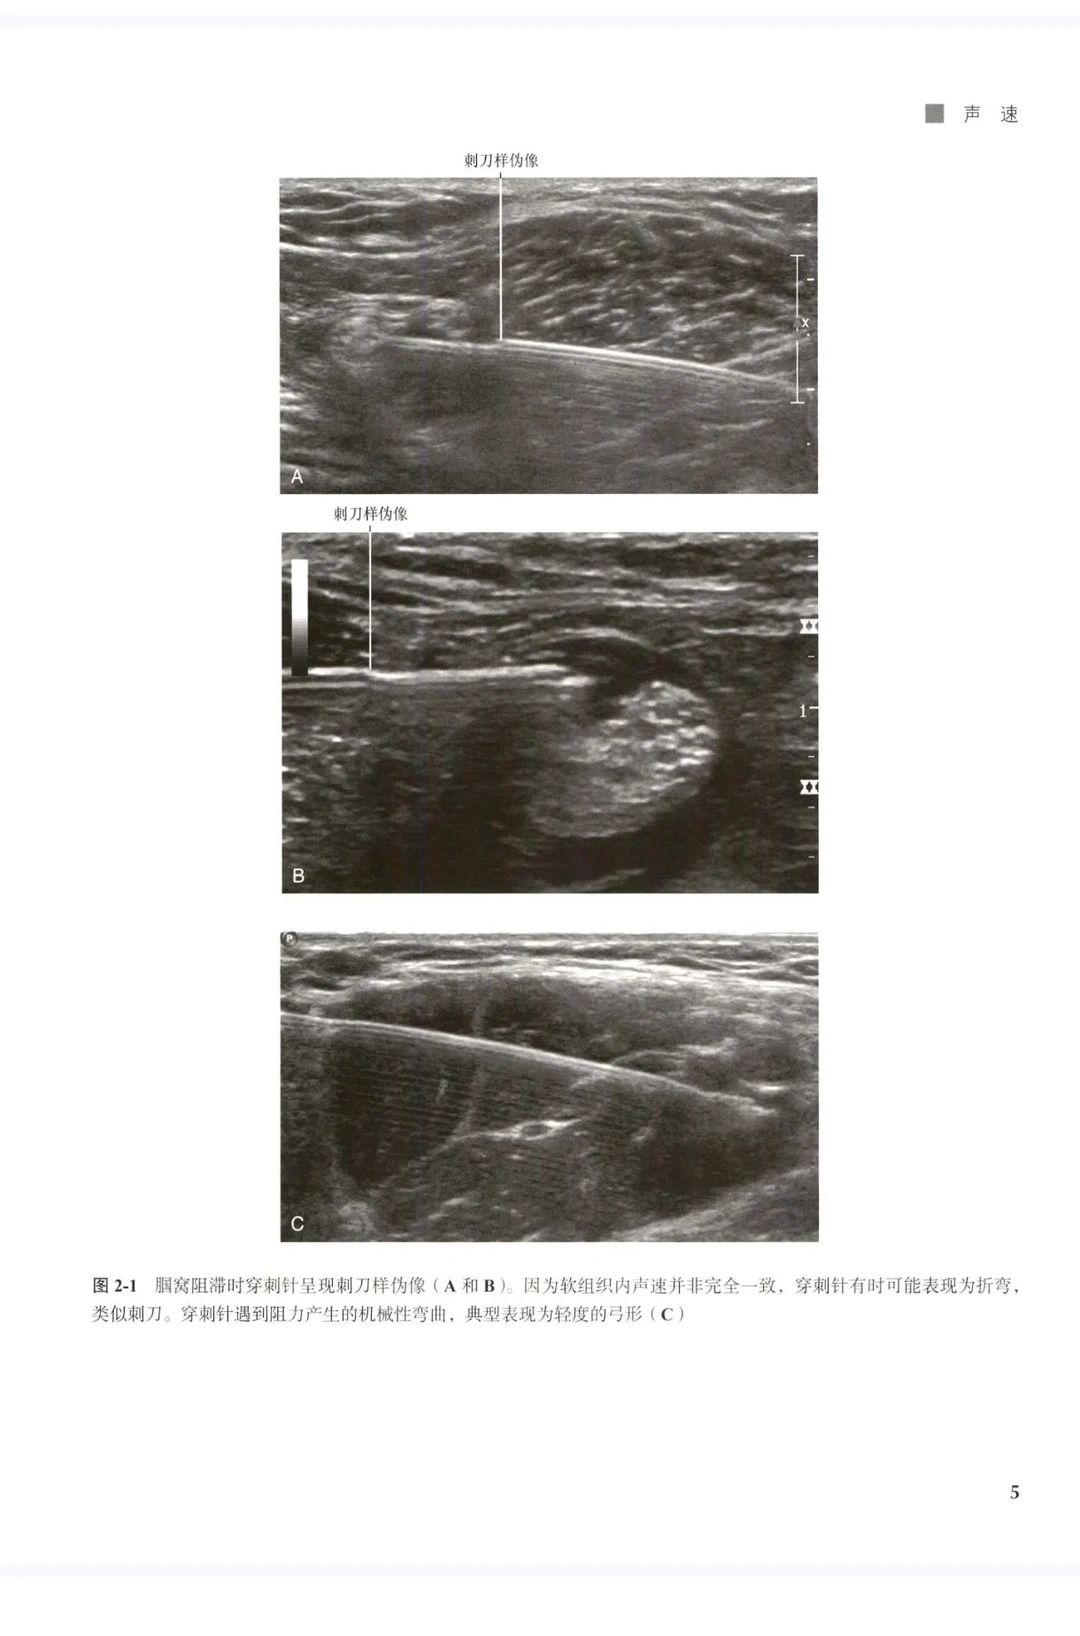

3. 高清直观,操作更轻松 收录超500幅高清体表+超声对照图,清晰呈现解剖变异、穿刺路径、神经定位细节,将抽象的解剖结构与超声图像精准对应,告别“看不清、找不准”的难题,新手能快速上手,老手能精准规避风险。